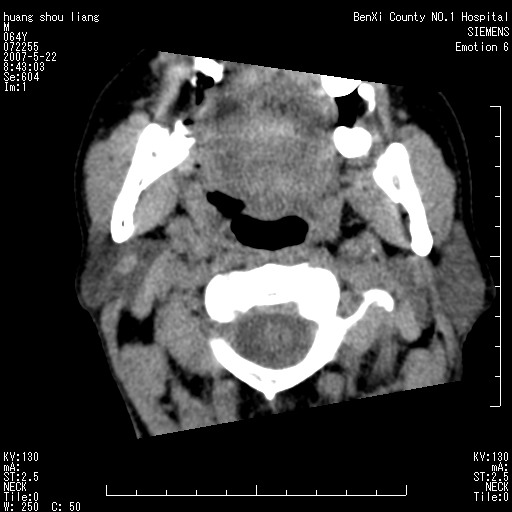

男性,64岁。颈部包块8年。最近增大。

对不起大家,可能是片子发太多有点乱,正常腮腺在下颌角的外侧,颌下腺在下颌体的中部内侧,本例在下颌角内侧偏下,和腺体一点关系都没有,从vrt和mpr上可以很明显看出来,再者肿块是好多粘连在一块的,大家在仔细看看,左侧可能也是吧,我还是考虑为肿大的淋巴结融合在一块,但性质??????

右侧腮腺下部均匀软组织密度肿块,外形不规则,与周围组织分界清晰,考虑右侧腮腺混合瘤或多形性腺瘤。

大家好,病理结果出来了,如大家所说,颌下腺混合瘤。

唉,解剖没学好吧,我诊断错了,不过还是有些不理解回去我在多看看书,谢谢大家的参与,以后我还会奉献好的病例。